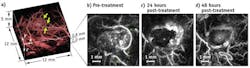

To study how a tumor and its surrounding blood vessels are affected by a therapeutic vascular disrupting agent, the researchers imaged, in-vivo, human colorectal adenocarcinoma xenografts in nude mice at different times using their all-optical photoacoustic scanner. In the setup, a fiber-coupled, wavelength-tunable, pulsed Nd:YAG optical parametric oscillator (OPO) laser system delivers 7 ns pulses at 50 Hz to the tissue under study. A Fabry-Perot (FP) sensor head used to detect the photoacoustic waves is placed in acoustic contact with the surface of the skin using an aqueous gel.

From the photoacoustic signals, 3D images are formed using a time-reversal image reconstruction algorithm that compensates for the acoustic attenuation characteristic of soft tissues through a frequency-dependent amplification that exactly counteracts the tissue absorption. This significantly improves image intensity and resolution—especially at greater tissue depths.

Photoacoustic images of a subcutaneous tumor treated with a therapeutic vascular disrupting agent were obtained both before and 24 and 48 hours after injection of the agent. Post-treatment images clearly show dynamic changes in the tumor vasculature due to the vascular shutdown that occurs over time, which results in strongly decreased perfusion particularly within the tumor core and thus reduced image contrast.